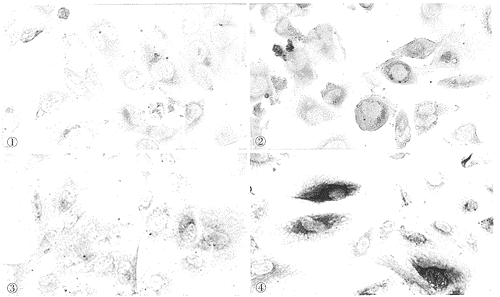

摘要 目的 探讨肿瘤坏死因子α(TNFα)对培养的人肾小球内皮细胞(HUGEC)表达单核细胞趋化蛋白-1(MCP-1)的影响以及HUGEC的条件培养基对单核细胞(MC)的趋化作用及抗MCP-1抗体对单核细胞迁移的影响。方法 (1)采用原位杂交技术、免疫细胞化学、细胞ELISA法观察MCP-1基因及蛋白表达。(2)用改良的Boyden小室微孔滤膜法测定TNFα刺激HCGEC后的条件培养基对MC的趋化作用及抗MCP-1抗体对MC迁移的影响。结果 (1)在不加刺激条件下培养的HUGEC弱表达MCP-1基因及蛋白,50ng/ml TNFα刺激后,6小时即有MCP-1蛋白表达增强,于12小时达高峰,不同浓度的TNFα(25、50、100ng/ml)刺激HUGEC6小时后,与正常对照组相比差异显著(P<0.01)。(2)TNFα刺激HUGEC后的条件培养基对MC有明显趋化作用,并被抗MCP-1抗体抑制。结论 HUGEC在TNFα诱导下,其MCP-1的表达增强,其条件培养基对MC有趋化作用,从而可能招引单核细胞迁入内皮下间隙。

Abstract Objective Tostudy the expression of monocyte chemoattractant protein-1 (MCP-1) in cultured humanglomerular endothelial cell (HUGEC).Methods The effect of TNFα on theexpression of MCP-1 mRNA and protein by HUGEC was observed with in situ hybridization,immunocytochemistry, cell ELISA analysis . The monocyte migration induced by the mediaconditioned by cultured HUGEC was assayed by micropore filter method using modified BoydenChamber. Influence of anti-MCP-1 antibody on monocyte migration was observed as well.Results mRNAand protein of MCP-1 were only basically expressed on HUGEC at very low levels in thecontrol groups without stimulation. After stimulation by TNFα (50 ng/ml), however,their expression was markedly upregulated from the 6th hour. The maximal proteinexpression of MCP-1 was present at the 12th hour. Compared with control groups, MCP-1protein expression was significantly increased after the stimulation at differentconcentration of TNFα (25,50,100ng/ml) stimulation (P<0.01). HUGEC stimulated by TNFαproduced a factor that was markedly chemotactic for monocytes , and the chemotacticactivity was inhibited by anti -MCP-1 antibody.Conclusion HUGECstimulated by TNFα may highly express MCP-1, and produce chemotactic factors formonocytes.